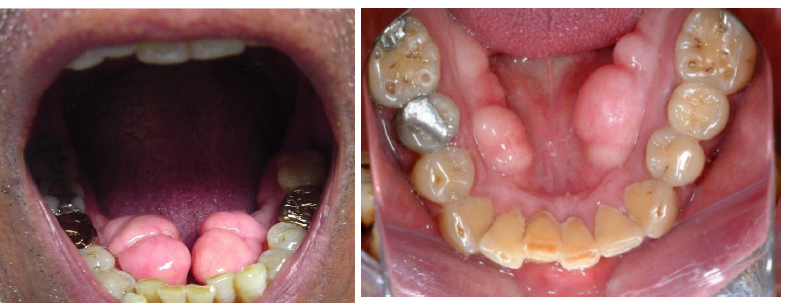

torus mandibularis

usually bilateral, in the premolar area